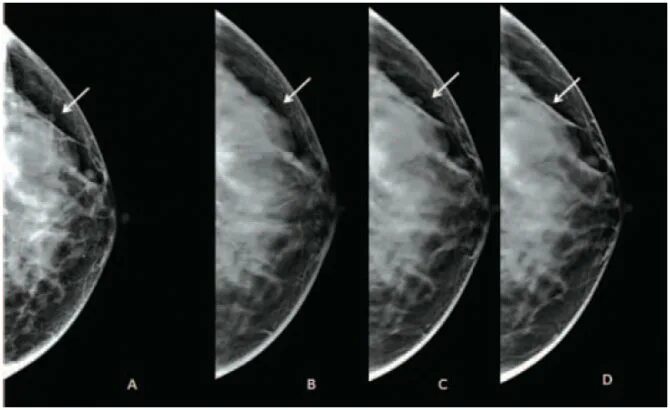

Сгруппированные микрокальцинаты